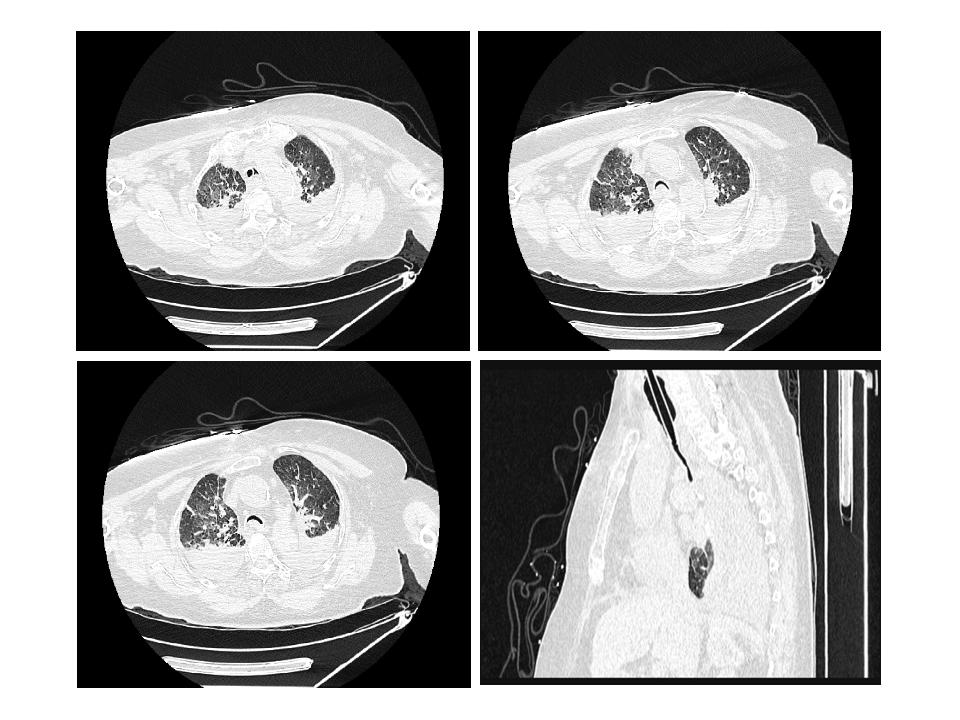

第二次就诊(2020年12月28日):因“突发气促伴意识不清10 min”呼叫120。到达现场时,患者无反应,口唇发绀,大动脉搏动消失,无自主呼吸,血压测不出,立即施行胸外按压、开放气道、球囊面罩通气、开放静脉通道,静注肾上腺素等抢救措施,心电图呈一直线,抢救约10 min后监测显示心电恢复,无颈动脉搏动及自主呼吸,予持续胸外按压、气管插管机械通气,转运至我院急诊。血常规:白细胞13.72×109/L,中性粒细胞百分比44.1%,肌钙蛋白Ⅰ 0.02 ng/mL,血钾5.3 mmol/L,钠138 mmol/L,血酮体0.12 mmol/L,D-二聚体33.88 mg/L,NT-pro BNP 1 204 pg/mL,高敏肌钙蛋白T 29 pg/mL。头颅及胸部CT平扫(图 2)示:(1)脑实质密度减低,脑实质肿胀,不除外脑水肿可能;(2)双侧椎动脉、颈内动脉颅内段硬化;(3)气管、主支气管及其分支退变,气管及双侧主支气管塌陷;(4)双肺慢性支气管炎,双肺多发间质性炎症,双侧胸腔少量积液,较前增多。复苏后心电图示窦性心律,心率98次/min。诊断呼吸心搏骤停、呼吸衰竭、慢性阻塞性肺疾病急性加重期,给予补液、抗感染、机械通气等治疗。至第二天患者家属放弃抢救,宣布死亡。

|

| 气管导管尖端至隆突段可见显著气管塌陷,膜部向管腔内过度凹陷 图 2 患者第二次就诊(2020-12-29)胸部CT平扫及三维重建图 |

|

|